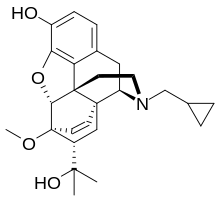

Oripavine derivatives

Thienorphine

- 7-PET

- Acetorphine

- Alletorphine (N-allyl-noretorphine)

- BU-48

- Buprenorphine

- Buprenorphine-3-glucuronide

- Cyprenorphine

- Dihydroetorphine

- Etorphine

- Homprenorphine

- 18,19-Dehydrobuprenorphine (HS-599)

- N-cyclopropylmethylnoretorphine

- Nepenthone

- Norbuprenorphine

- Norbuprenorphine-3-glucuronide

- Thevinone

- Thienorphine

Structures

| Oripavine derivatives | ||||

7-PET 7-PET |

Acetorphine Acetorphine |

Alletorphine Alletorphine |

BU-48 BU-48 |

Buprenorphine Buprenorphine |

Cyprenorphine Cyprenorphine |

Dihydroetorphine Dihydroetorphine |

Etorphine Etorphine |

Homprenorphine Homprenorphine |

18,19-Dehydrobuprenorphine 18,19-Dehydrobuprenorphine |

N-cyclopropylmethylnoretorphine N-cyclopropylmethylnoretorphine |

Nepenthone Nepenthone |

Norbuprenorphine Norbuprenorphine |

Thevinone Thevinone |

Thienorphine Thienorphine |